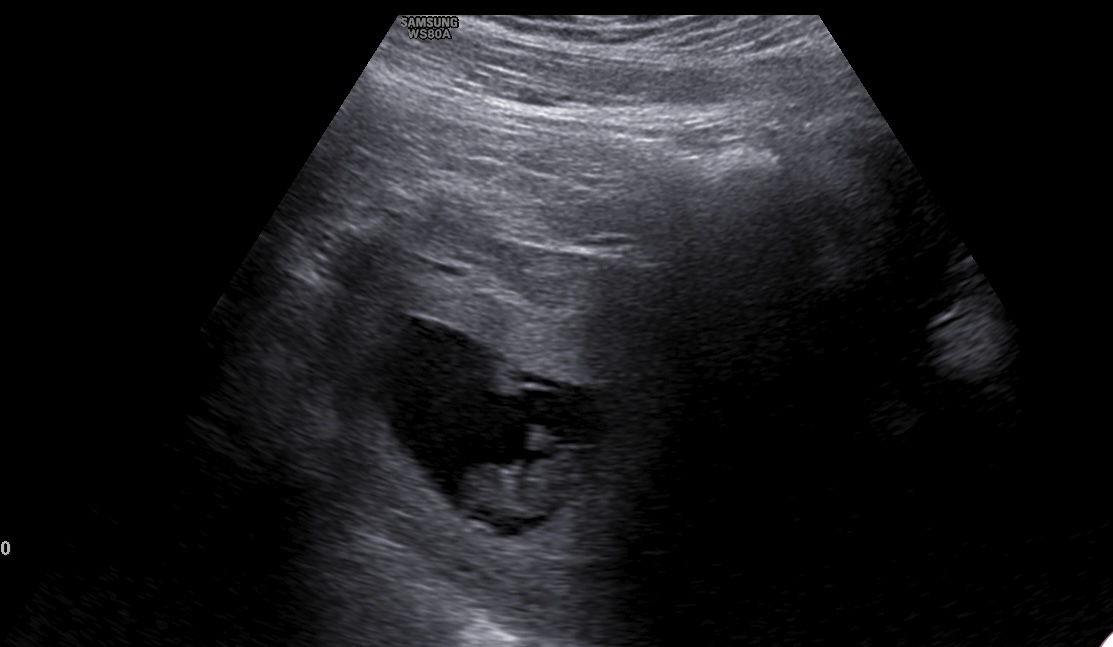

I went for my first US, apparently the placenta and the baby are both placed on the wrong positions. The placenta is below and the baby is up whereas it is supposed to be the other way round. It's called placenta previa. Has anyone ever came across such, is it something to worry about? The midwife was not too worried about it because i give birth through c-section. Below is the scan, the placenta can be seen down there that it has blocked the baby completely.